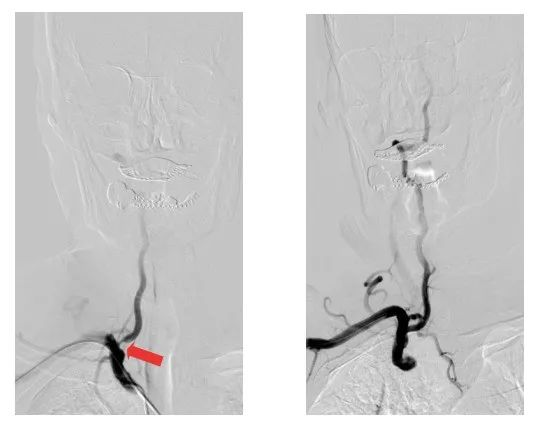

術(shù)前術(shù)后影像對比(紅色箭頭所指位置為狹窄處)

醫(yī)療團隊僅用時40多分鐘,便通過右側(cè)橈動脈入路,成功在患者的椎動脈置入1枚支架。術(shù)后,患者的椎動脈狹窄解除,頭暈頭痛癥狀消失,即可下床活動,身體恢復(fù)良好。